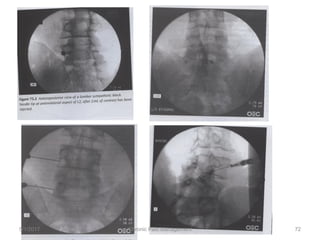

EPIDURAL INJECTIONS:

Lumbar interlaminar epidural injections

Fluoroscopic injections

Transforaminal injections

Radiofrequency rhizotomy

5/1/2017 72Chronic Pain Management